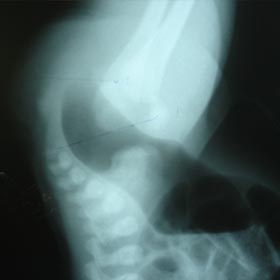

Intestinal Obstruction

All types of intestinal obstruction are treated with very good results provided the patients are referred early. During my tenure, I have seen all kinds of complications related to intestinal obstructions and treated with very high success rate.